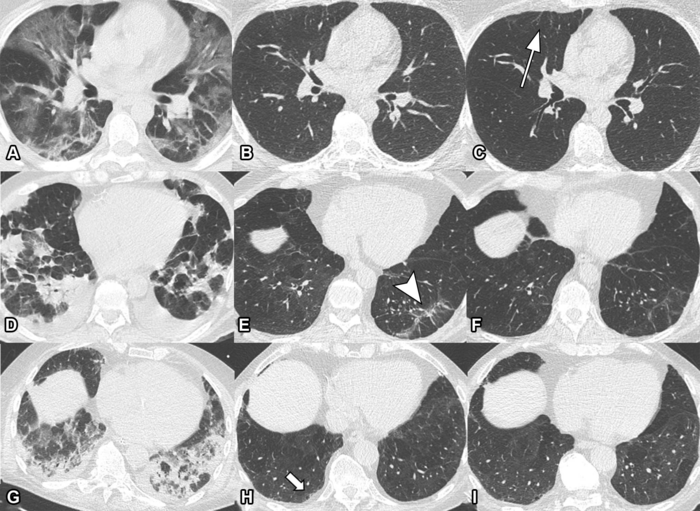

This photo gallery shows the variety of radiological presentations of COVID-19 (SARS-CoV-2) in medical imaging, including computed tomography (CT), radiograph X-rays, ultrasound, echocardiograms and magnetic resonance imaging (MRI). The radiology images show examples of typical COVID pneumonia in the lungs and the numerous complications the virus causes in the body in multiple organs, including the brain, kidneys, heart, abdomen and vascular system.